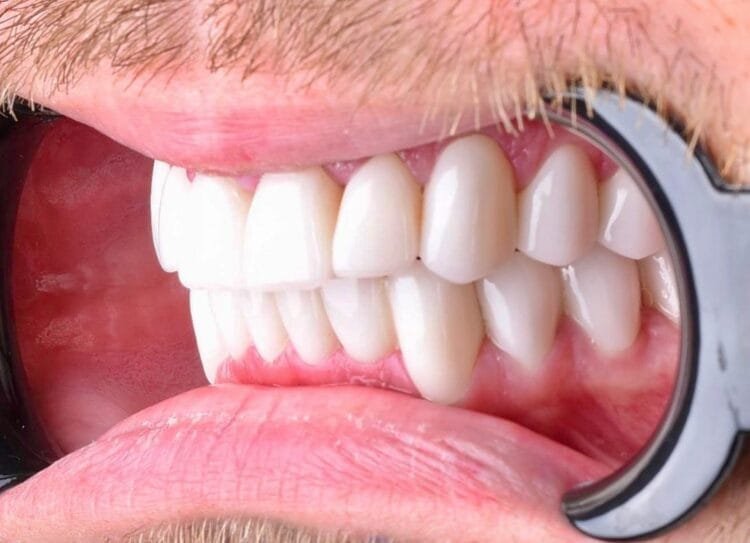

Ich habe meine Doktorarbeit an der Gazi Universität, Abteilung für Prothetik, zum Thema "Der Einfluss verschiedener Zementfarben auf die Farbe bei vollkeramischen Restaurationen" geschrieben. Ich habe mein Fachwissen durch akademische und wissenschaftliche Studien vertieft.

Mit meinem Promotionsverfahren an der Gazi Universität biete ich Dienstleistungen mit einem wissenschaftlichen Ansatz in der ästhetischen und prothetischen Zahnbehandlung an. Jeder Behandlungsplan wird auf der Grundlage aktueller wissenschaftlicher Erkenntnisse gestaltet.

Ich plane speziell für die Bedürfnisse jedes einzelnen Patienten und arbeite akribisch bis ins kleinste Detail, um Ihnen ein natürliches und ästhetisches Lächeln zu ermöglichen.